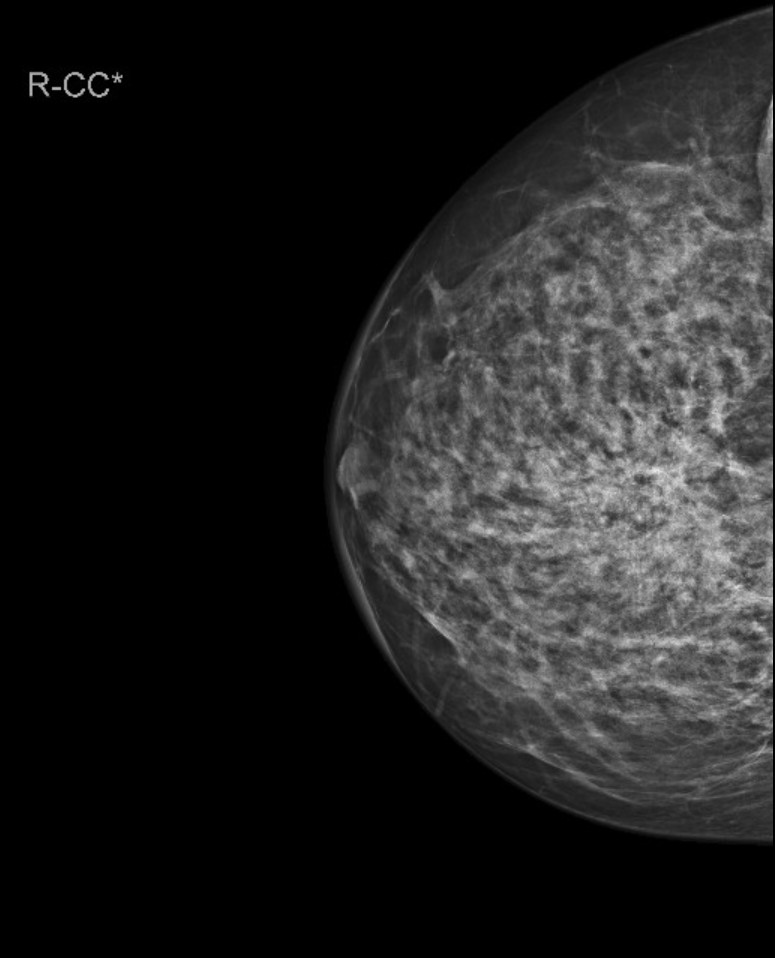

Vorsorgemammographie. Zum Zweitbefunden. Welche BIRADS Einstufung wählen Sie? (Anmerkung: 0 gilt nicht!).

Wenn Sie etwas anderes als 1 wählen, geben Sie die Veränderung mit Seite und Beschreibung gemäß BIRADS an!

Natürlich kann auch mal ein Normalbefund dabei sein! Aber vielleicht auch nicht!